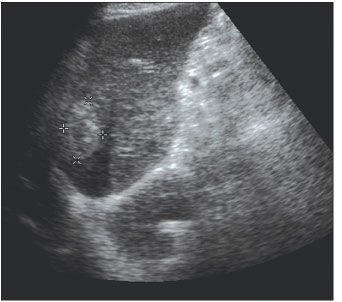

Figure 2. Abdominal ultrasonogram showing a mass (marked area) in the left lobe of the liver in an HIV/hepatitis C virus-coinfected man with hepatocellular carcinoma.

Since the beginning of the HAART era in 1996, there has been a noticeable increase in HCC among HIV-infected persons who are coinfected with hepatitis C virus (HCV) or hepatitis B virus (HBV) (Figure 2).59,60 Rosenthal and colleagues,61 in a French survey of causes of liver-related death in HIV-positive persons, demonstrated an increase in liver-related mortality due to HCC from 4.7% in 1995, to 11% in 1997, to 25% in 2001. Several cancer registry studies comparing HIV-positive with HIV-negative persons with malignancies have recently demonstrated a 4- to 30-fold increased risk of HCC among HIV-positive persons.5,6,62 In a large prospective cohort of 63,000 HIV-positive persons throughout the United States, HCC developed in 49 of the patients from 1992 to 2002.5 This was 4.5 times the rate expected in the general population. Galceran and colleagues6 found a 29-fold increase in HCC among a cohort of Spanish HIV-positive persons.